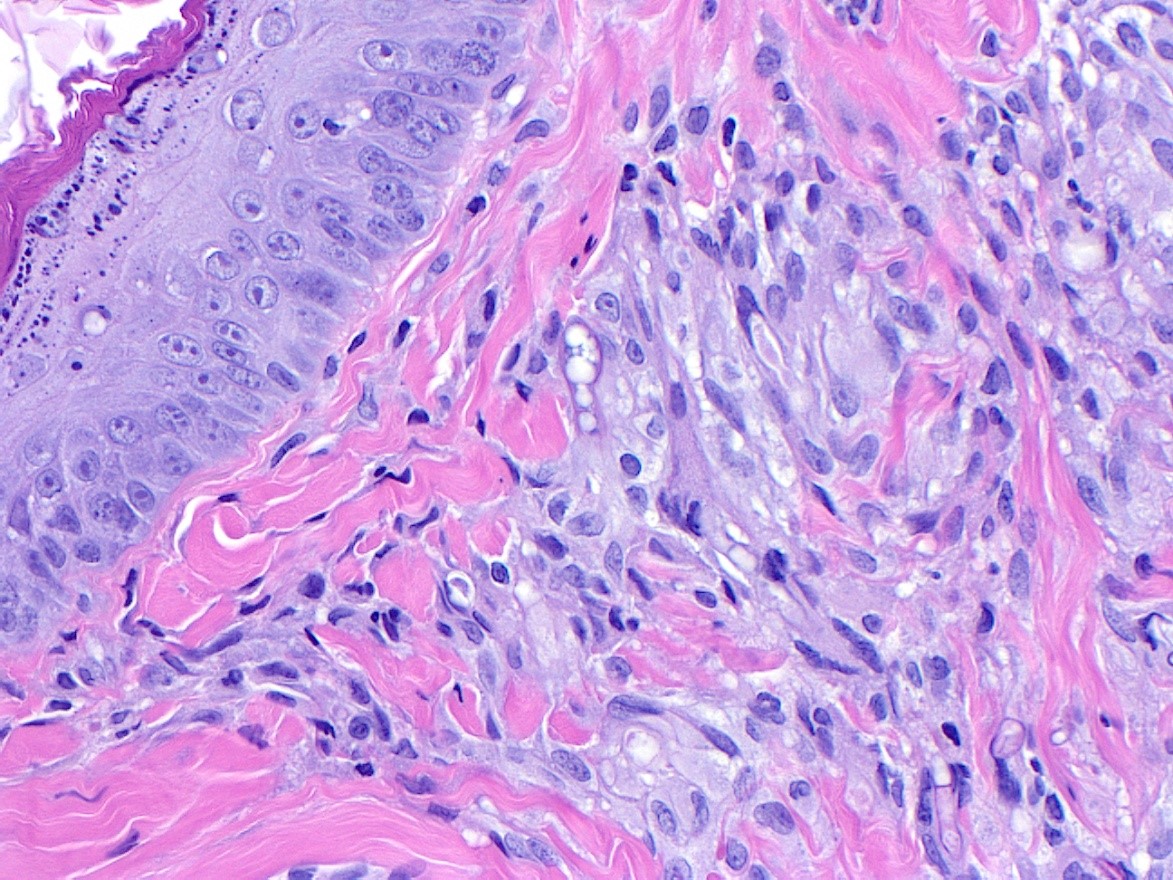

Figure 6. H&E, 10x magnification |

Figure 7. H&E, 20x magnification.